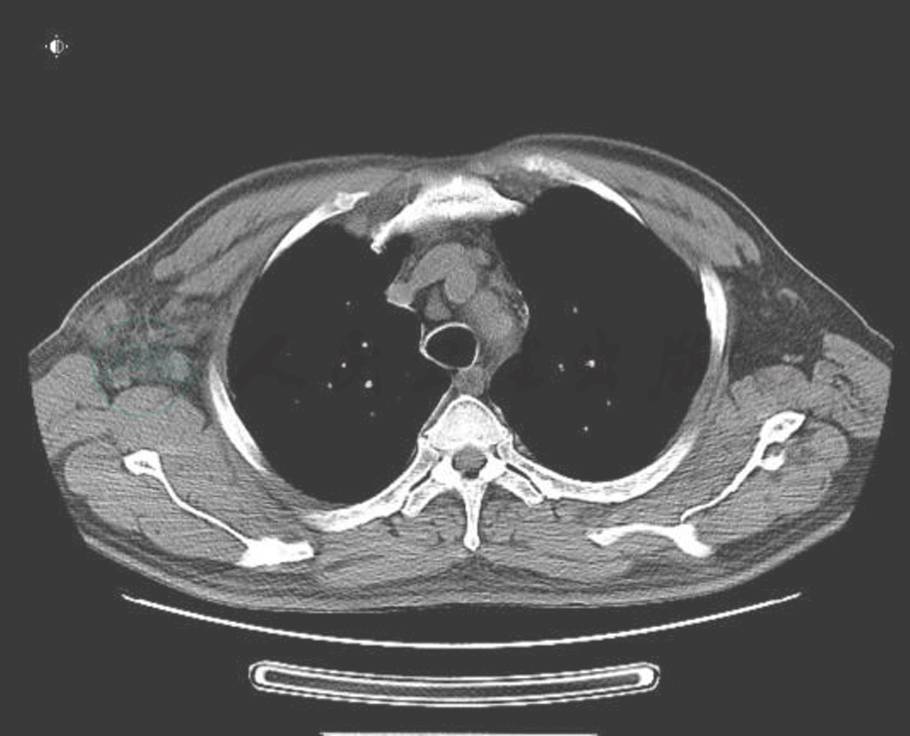

血象、血沉、结核三项、G试验、呼吸道病原及风湿免疫检查均未见异常。T-SPOT阳性。IgG 1410mg/dl,IgG4 355mg/dl。胸腔积液:送检胸水涂片及细胞病理学未见阳性结果;常规生化结果考虑为渗出液。胸部CT:右侧胸壁软组织占位并肋骨破坏及纵隔、腋窝淋巴结多发转移,不除外胸壁来源的恶性肿瘤;双肺炎症(图2、图3、图4)。小器官超声:双侧腋下多发肿大淋巴结。我院病理会诊(外院腋窝淋巴结标本):其内见血管内皮细胞增生显著。我院右侧腋窝淋巴结活检病理:Castleman病(巨大淋巴结增生症),透明血管型。免疫组化染色结果:CD3(T 细胞 +),CD20(B 细胞 +),CD21(+),CD34(血管 +),CD38(+),Ki-67(+25%~50%)。我院病理会诊(外院胸壁皮肤标本):考虑血管源性肿瘤,以上皮样血管内皮细胞瘤可能性大。我院右胸腹部皮肤活检:不除外血管肉瘤。北京协和医院病理会诊:(外院淋巴结):淋巴结结构存在,淋巴滤泡生发中心缩小,滤泡间见较多浆细胞浸润伴小血管增生。(外院皮肤):真皮胶原纤维及小血管显著增生,伴少许淋巴细胞浆细胞浸润;结合免疫组化考虑为IgG4相关性疾病,建议结合临床并作相关检查及测定血清IgG4水平。(我院淋巴结):CD138(+)、CD38(+)、IgG4/IgG(大于 40%)、IgG4(100 个 /HPF)。(我院皮肤):CD138(+)、CD38(+)、IgG45、IgG4(100 个 /HPF)。诊断考虑:淋巴结:Castleman disease。皮肤:不除外高分化血管肉瘤。

图3 治疗前(胸水和软组织肿胀)